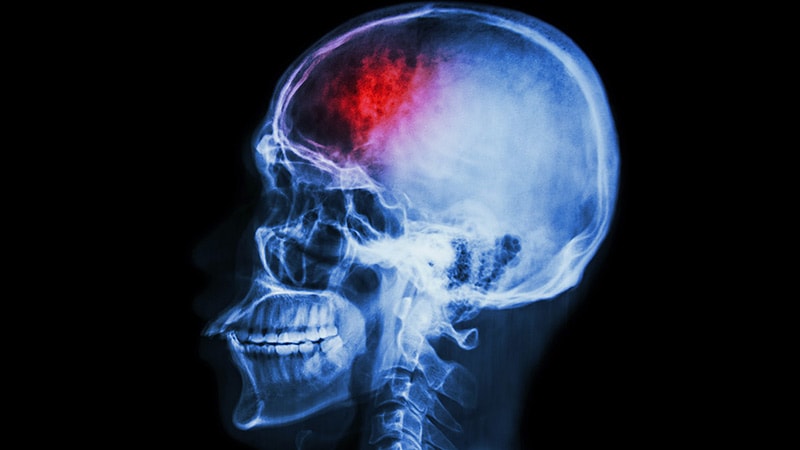

Restarting Antiplatelet After ICH Cuts Recurrence Risk in HalfRestarting antiplatelet therapy after intracranial hemorrhage remains controversial, but new evidence suggests aspirin or

clopidogrel can significantly reduce recurrent ICH without increased bleeding.